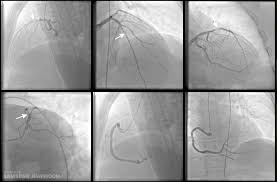

- 심장 원인: 응급처치 후 혈관확장제, 스텐트, 수술 등 전문 치료